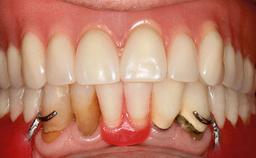

An 83-year-old man presented together with his caregiver at the dental department of the Medical University of Innsbruck, Austria with complaints of swelling in the right maxillary canine area and loss of retention of his 5-years-old mandibular denture. The patient had a significant medical history (20 years) of bipolar affective disorder with moderate depression (F 31.3) and dementia in Alzheimer’s disease (F 00.2). The patient had been in ambulant psychiatric therapy for his depressive illness for the past 20 years. He lived alone and had no children; his sister assisted with daily living. She reported that the patient exhibited compulsive hoarding behavior. In the previous two months, she had noted increasing disorientation and vertigo in the patient. She therefore accompanied him for a medical consultation at the Department of Psychiatry and Psychotherapy of the Medical University of Innsbruck. He was released home after a 6-week inpatient stay.

Periodontal Status History of periodontitis or genetic predisposition

Oral Hygiene and Compliance Insufficient